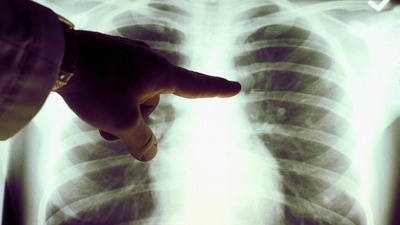

Akciğer kanserini erken evrede yakalamak için bilinçli yaklaşım ve kişiye uygun check-up yapılması gerekiyor ve bunun da akciğer filmi ve düşük doz akciğer tomografisi ile gerçekleştirilmesi gerektiğine dikkat çekiliyor. Uzun süredir tütün ve tütün ürünü kullanan 40 yaş üstü kişiler ile ailesinde akciğer kanseri hikâyesi olanların düzenli hekim kontrolünde olmaları gerekiyor. Risk altında olan bu kişilere düşük doz akciğer tomografisi öneriliyor. Eğer çok küçük boyutta bir lezyon tespit edilirse (genellikle akciğerde nodül olarak tanımlanıyor) akciğer 3 veya 6 ayda bir düşük doz tomografi ile takip ediliyor. Bu noktada hastaların radyasyona maruz kalmamaları için tomografi dozunun düşük olması büyük önem taşıyor. İlaçsız çekilen tomografide bile hastanın radyasyon aldığının unutulmaması gerekiyor.